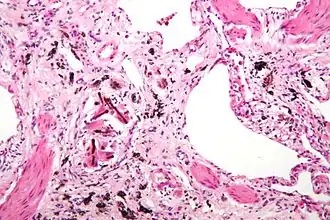

Пневмокониоз (лат. pneumon — лёгкие и konia — пыль) — группа заболеваний лёгких (необратимых и неизлечимых)[2], вызванных накоплением в лёгких достаточно большой дозы нерастворимой производственной пыли, вызывающей развитие в них фиброзного процесса[3]. Пневмокониозы относятся к профессиональным болезням. Начальные стадии не выявляются при флюорографии и могут быть обнаружены при вскрытии при вредном стаже менее 1 года[4]. Встречаются у рабочих горнорудной, угольной[5], машиностроительной и некоторых др. отраслей промышленности.

Жалобы: непродуктивный кашель, прогрессирующая одышка. Развивается цирроз лёгкого, сморщивание лёгочной ткани с участками эмфиземы.